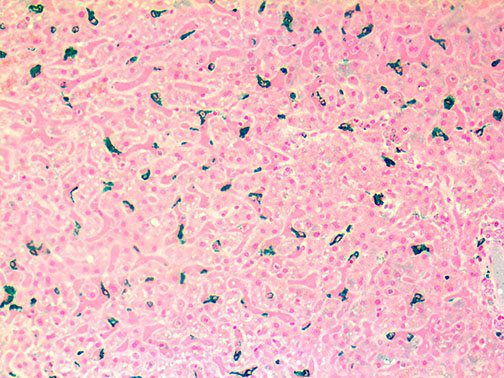

Clinical and laboratory manifestations of HLH include fever, enlarged liver and/or spleen, neurologic dysfunction, coagulopathy, liver dysfunction, cytopenias (i.e., low levels of erythrocytes, leukocytes, and/or platelets), hypertriglyceridemia, hyperferritinemia, hemophagocytosis, and eventually diminished NK cell activity as the immune system becomes progressively paralyzed. HLH can be familial (primary HLH) or secondary to another disease process (sHLH), such as rheumatic disease, in which it is referred to as macrophage activation syndrome (MAS, characterized by elevated ferritin).

This activation induces inflammatory monocytes to highly express IL-6, starting a localized and then systemic cascade effect that results in hyperproduction of IL-6, which accelerates the inflammatory process. Because IL-6 also increases vascular permeability, excessive levels cause blood vessels to become very leaky. This, along with clotting factors released from vascular endothelial cells, stimulates the coagulation cascade, resulting in microthrombosis (tiny clots), which leads to ischemia and tissue death of the kidney, intestines, heart, liver, brain and extremities.